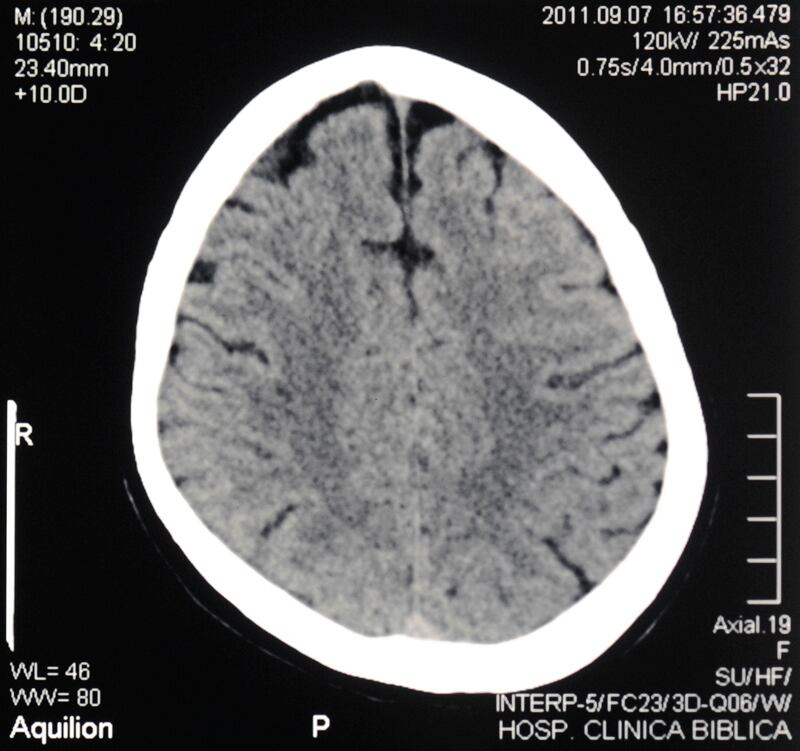

Para el médico Franz Chaves Sell , especialista en neurología de la Clínica Bíblica, es infinitesimal lo que conocemos del cerebro hasta el día de hoy. Como factores que han dificultado esa mayor aproximación, cita sus complejas redes neuronales y el hecho de que las funciones cerebrales no están localizadas en un sitio en particular, sino que son producto de las activaciones de ese entramado de redes.